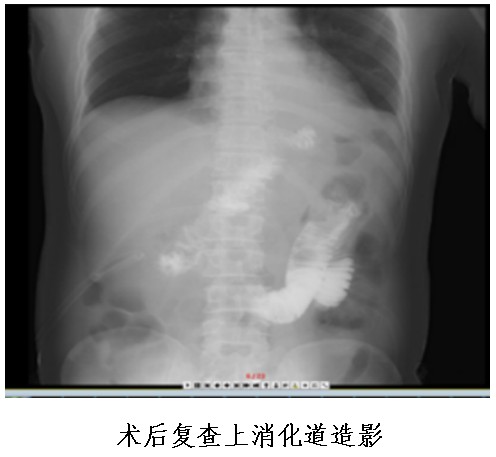

①食管空腸吻合口;

②殘胃空腸吻合口;

③空腸空腸吻合口。

其中,食管空腸吻合口距殘胃空腸吻合口15-20cm,殘胃空腸吻合口距空腸空腸吻合口15—20cm。

食物通過(guò)食管空腸吻合口后,一部分通過(guò)胃空腸吻合口進(jìn)入遠(yuǎn)端胃、十二指腸及小腸,另一部分食物直接進(jìn)入小腸,故稱之為“雙通道”消化道重建。

該吻合方式通過(guò)增加了一個(gè)殘胃與小腸的食物通道,可以防止胃酸直接反流進(jìn)入食管,而遠(yuǎn)端胃和原有消化通道的保留,可以維持胃與十二指腸的部分功能,成功解決近端胃切除術(shù)后患者胃食管返流、胃癱及遠(yuǎn)期營(yíng)養(yǎng)障礙的問(wèn)題,大大提高術(shù)后患者的生活質(zhì)量。